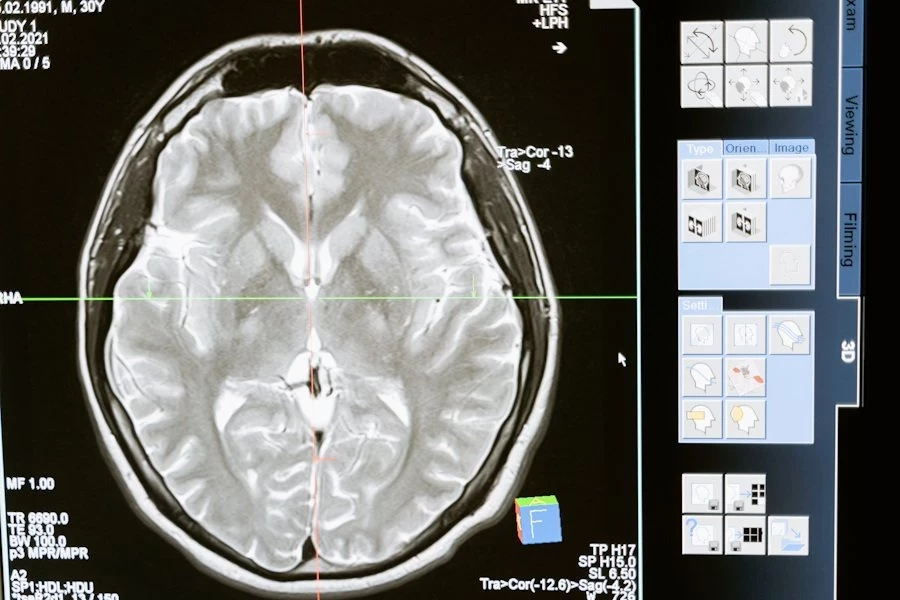

Главным препятствием является неспособность человеческого мозга переживать длительное отсутствие кислорода. Уже через несколько минут после остановки кровообращения клетки мозга начинают необратимо разрушаться. В то время как другие органы, такие как сердце или почки, разрушаются медленнее, что позволяет использовать их для трансплантации, мозг остается самой уязвимой частью организма.

Наука делает огромные шаги вперед в области трансплантации органов, но возрождение жизни из небытия по-прежнему остается за гранью возможного. Как заметил Скальный, сохранение структуры клеток и тканей, особенно мозга, – главная проблема, которую пока не может решить ни одна современная технология.